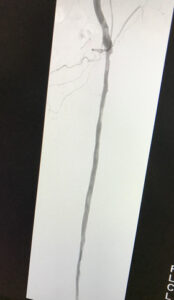

Ενδαγγειακή αποκατάσταση απόφραξης της επιπολής μηριαίας αρτηρίας

ελάχιστα παρεμβατική μέθοδος

24 ωρη παραμονή

Ενδαγγειακή επαναγγείωση της επιπολής μηριαίας αρτηρίας

πλήρη ύφεση της συμπτωματολογίας